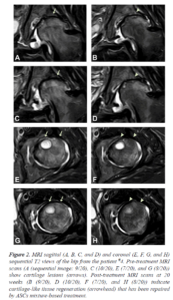

2. 슬개골 연골연화증 연골재생 치료: Regeneration of cartilage in chondromalacia patellae patients. A novel biological approach to treat chondromalacia patellae. PLoS ONE 8(5): e64569. http://www.plosone.org/article/info%3Adoi%2F10.1371%2Fjournal.pone.0064569

3. 반월상연골판 연골파열 연골재생 치료: Review Article”Regenerative Repair of Damaged Meniscus with Autologous Adipose-Tissue-Derived Stem Cells,” BioMed Research International, vol. 2014, Article ID 436029, 10 pages.http://www.hindawi.com/journals/bmri/2014/436029/